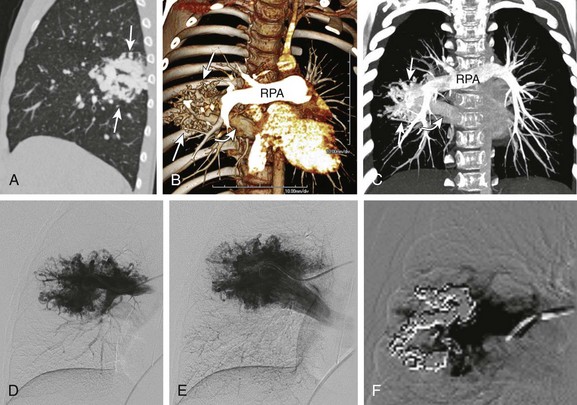

Figure 53-30 A hybrid lesion, intralobar sequestration, and microcystic maldevelopment (congenital pulmonary airway malformation [CPAM] type 2).

A, A transverse fetal ultrasound image shows a large left lower lesion (arrows) resulting in significant cardiac heart (H) and aortic (asterisk) displacement. Internal cystic components are noted mainly at the periphery of the lesion. B, An axial T2-weighted fetal magnetic resonance image shows the extensive hyperintense lesion within the left lower lobe. Cystic peripheral components consistent with CPAM are noted (arrowheads). An aortic feeder (curved arrow) is seen supplying the lesion. S, Spine. C-F, Postnatal imaging shows a complex, partially aerated left lower lesion supplied by an aberrant aortic vessel (curved arrows) with aerated, mainly peripheral cysts (asterisks) and overall findings consistent with a hybrid lesion (arrows). The lesion appears relatively smaller when compared with the prenatal images. Volume-rendered (C), maximum intensity projection (D), and axial computed tomography angiography (E and F) images show a systemic, aortic feeder (curved arrows) to the lesion (arrows). Internal cystic components are noted predominantly at the periphery (asterisks) of the lesion. A portion of unaerated lung is seen at the base of the lesion. G, A coronal reformatted minimum intensity projection image shows the internal cystic components of the CPAM (arrows) to better advantage.